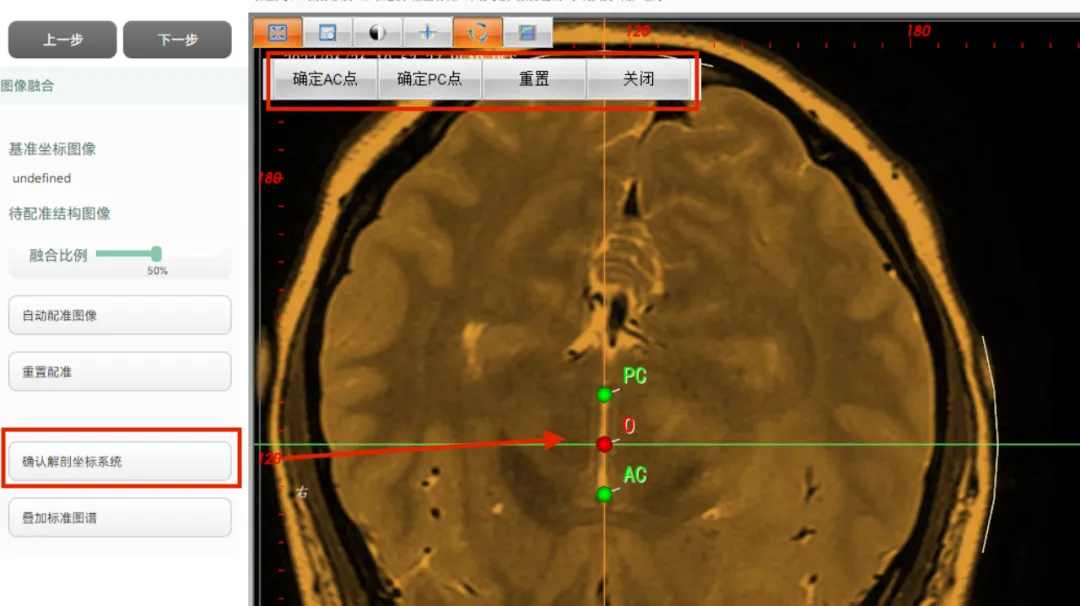

图像融合

导入多个序列,可对图像进行一键融合,生成融合序列,如:进行CT、磁共振融合,设定融合比例,可对CT或磁共振显示的权重进行调整。

可以通过确定AC、PC点,构建解剖坐标系,进行功能性手术,并且本软件内置常用功能靶点坐标,具体坐标数值可根据医生的经验进行编辑调整,构建好解剖坐标系后,在手术规划中,即可调用功能靶点。